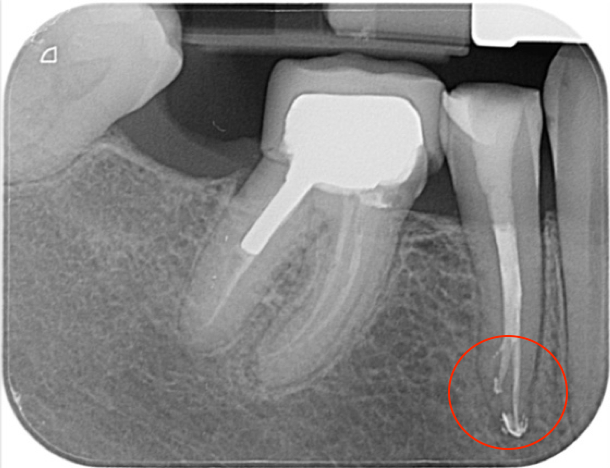

Below is the radiograph (displaying nice healing) taken at her 1-year review appointment, where the patient reported the tooth was symptom-free, which was pleasing: